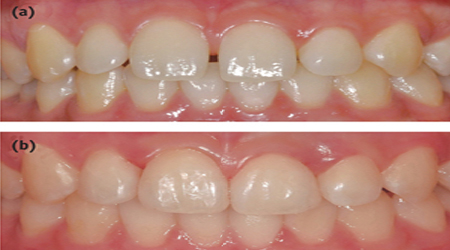

Child Dentistry

Smile For Children